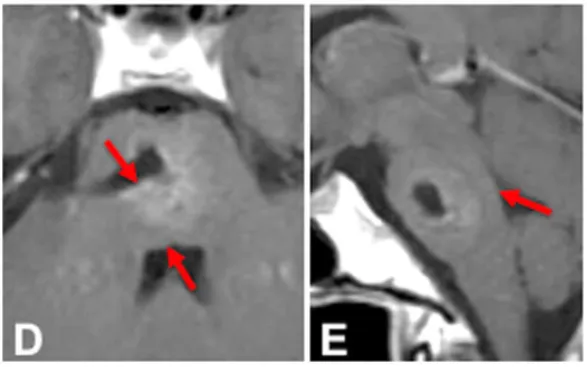

术后影像上记录了切除情况,病灶得到全切(D和E)。减压后,切除腔背侧的脑桥实质已明显展开并恢复了明显的宽度(红色箭头)。